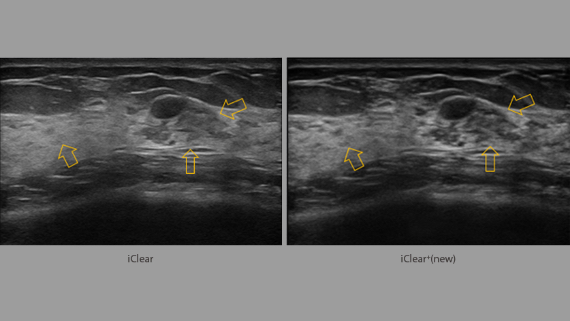

Obrazy kliniczne